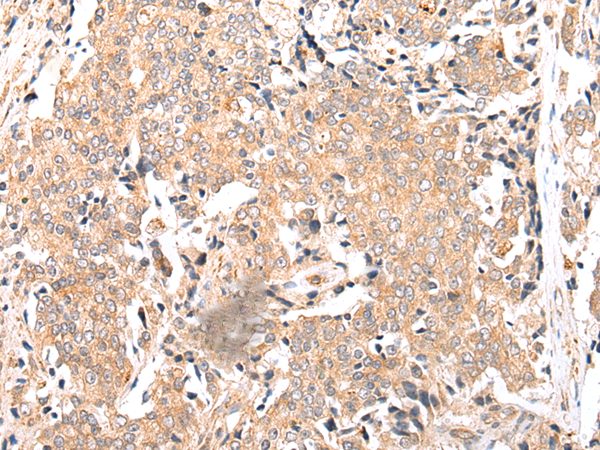

The image is immunohistochemistry of paraffin-embedded Human gastric cancer tissue using P05656(FPR1 Antibody) at dilution 1/20. (Original magnification: ×200) |

The image is immunohistochemistry of paraffin-embedded Human prostate cancer tissue using P05656(FPR1 Antibody) at dilution 1/20. (Original magnification: ×200) |